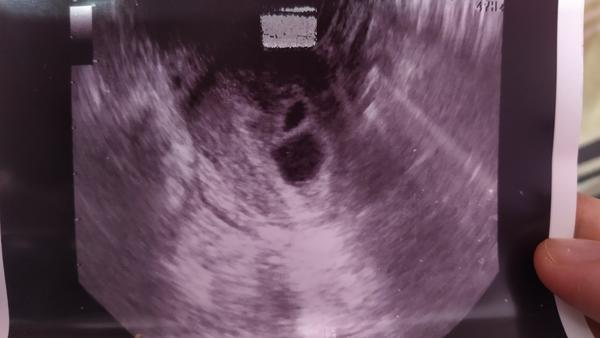

Prosím váš názor - 2 dutinky na sone

Ahojte. Chcela by som vediet váš názor. Prvé sono urobeny 28.4. a druhý dnes 7.5... 28.4.som mala len jednu dutinku a dnes už 2.. plod bohužiaľ nie je prítomný len váčok, podľa vás je možné že v druhej sa ešte objaví plod? Podľa doktora 100% že nie a podla neho mám ísť urgentne v pondelok na kyret,ale ja by som ešte chcela počkať, ale on o tom nechce ani počuť...Podla poslednej MS mám 8+3tt ale mám veľmi nepravidelný dlhší cyklus takže nedá sa určiť presne. Ďakujem za každý názor 🙏

Žienky , a prosím neviete že ako je to možné ze od minulého týždňa sa mi vytvorila ešte jedna dutinka (a je už väčšia ako tá prva) ? Lekár na to povedal že on to nevie, a nemám to riešiť keďže tam nepočuje srdiečko...

Podla mna prve moze byt anembryomola s minuleho cyklu a druhe zdrave tehotenstvo... prosim pockaj este... nie som lekar, ale sama viem, ake to je, ked sa ti ovulacia posunie dva tyzdne a potom kazdy lekar len "ake je to male"... Momentalne ta to nijako neohrozuje, takze si stoj za svojim, ze chces tyzden pockat.